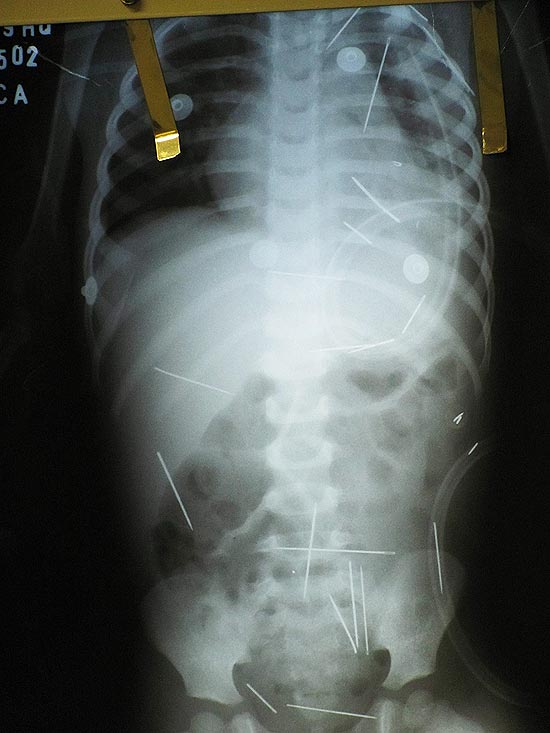

Era Angelina Capistana Ribeiro dos Santos que, em transe, durante o ritual de magia negra ordenava que Roberto Carlos Magalhães Lopes enfiasse as agulhas no corpo de seu enteado de apenas dois anos. O “trabalho” visava provocar a separação de Roberto e mãe do menino e a cada sessão eram colocadas de três a quatro agulhas, que provocava muita dor no garoto.

Uma mulher que se diz mãe-de-santo, e também presa, assistia a tudo. Maria dos Anjos Nascimento preparava o que considerava ser antídotos que aliviassem a dor da criança. A cirurgia marcada para hoje em Barreiras foi adiada, porque duas agulhas se alojaram no coração. O garoto foi transferido para Salvador, está sendo submetido a exames e sua operação contará com um especialista de coração. Seu estado é considerado grave. O padrasto disse que ao todo foram introduzidas 42 agulhas na criança.